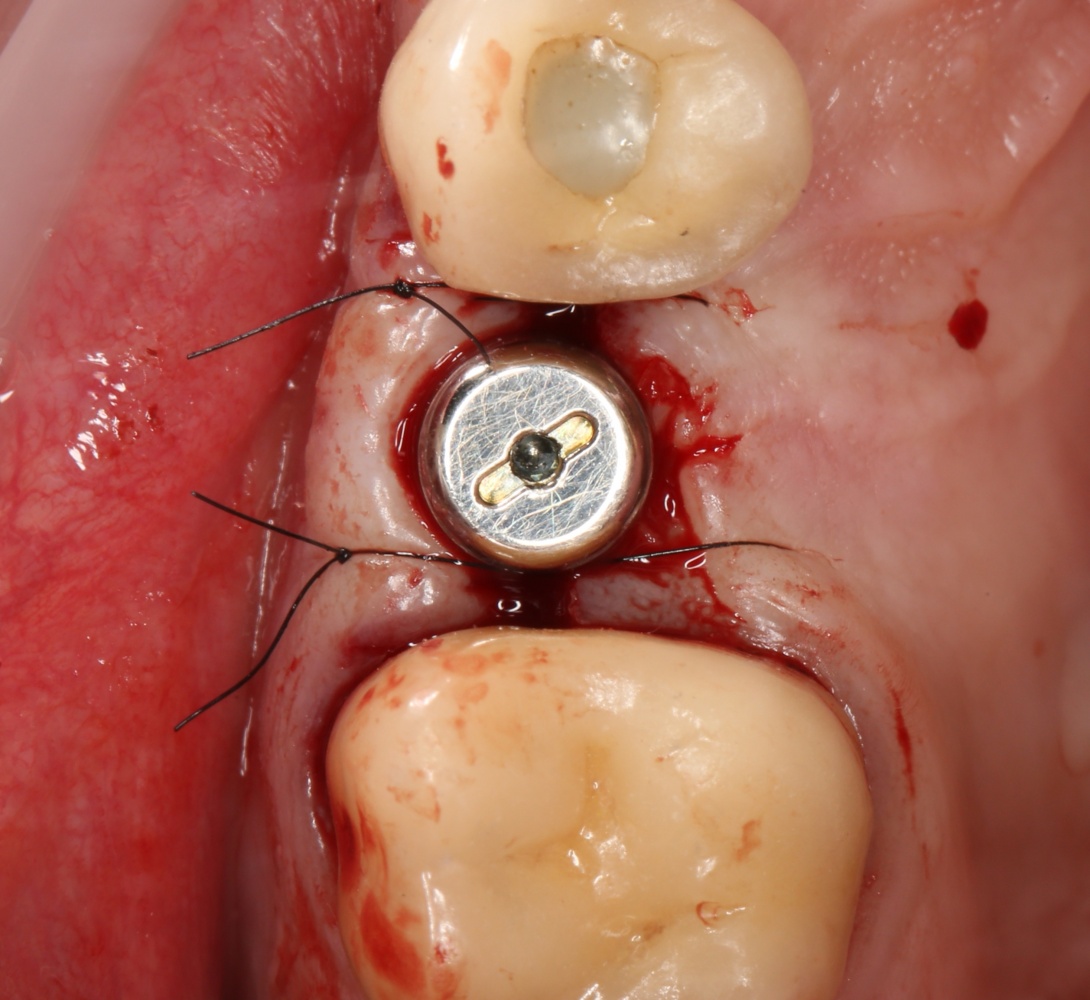

Наложение швов.

Если на этапе разреза и формирования раны всё сделано правильно, то наложение швов не вызывает особых трудностей. Периостотомия или послабляющие разрезы на периосте не требуются (ни практически никогда не требуются). А сами швы получаются аккуратными и герметичными:

Обрати внимание, что все шовные лигатуры находятся в пределах кератинизированной десны. Это позволяет избежать деформации тканей и лишних рубцов. В наиболее уязвимых местах (около зубов) шовные лигатуры лучше продублировать.

Устанавливаем формирователи десневой манжеты. Сегодня я называю эту процедуру не менее важной, чем любой другой этап имплантологического лечения:

И швы. Просто швы. Никаких дополнительных процедур.

Если честно, то сейчас бы я использовал другой шовный материал и другой тип швов. Одно неизменно, — и я об этом много раз говорил, — самая широкая часть формирователя десны должна находиться на уровне десны. Так, чтобы эффективно отрабатывать т. н. «биологическую ширину».